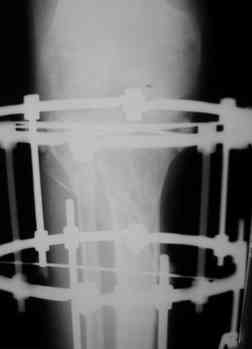

Опять мало информации. Это снимки от августа 2006. А что сейчас в двух проекциях? Что растет в посевах? Насколько заинтересован коленный сустав: движения, синовит? Чего хочет больной?

Р-граммы за март и апрель

Р-граммы и фото за 4.05.2007 - 7-е сутки после операции.

Ход операции - линейным разрезом по передней поверхности голени обнажена зона ложного сустава большеберцовой кости. От кости отсепарованы медиально м/ткани. Из зоны ложного сустава убраны рубцовые ткани, мобилизован дистальный отломок. По передней поверхности удалены два осколка, связанных грануляциями. Произведено удаление грануляционной ткани из проксимального отломка (на вид сине-серого цвета), "чистого" гноя не было. Затем произведено наложение аппарата и репозиция отломков. По передне-медиальной поверхности образовался дефект до 4х2х2 см + полость в проксимальном отломке. Удаленные осколки очищены от грануляций, уложены в место дефекта, зажаты между отломками. После иссечения раны по передней поверхности, находящейся рядом с операционной раной, последняя ушита с большим натяжением.

Перелом мыщелка сросся. Проксимальный отломок очень порозный.

Аппарат видел, репозиции не заметил. О "наложенном" аппарате: спицы в проксимальном отломке б\берцовой кости проведены очень низко, и опять только две, как и в первом аппарате. Почему только одна спица в дистальном парафрактурном кольце? Проксимальная база на бедре должна улучшить стабильность проксимального фрагмента tibia? Ничего подобного двумя спицами в одной базе при таком длинном рычаге вы не добьетесь, а вот совсем потерять движения в коленном суставе они почти гарантируют.

О репозиции: мыщелок сросся и слава Богу, но основные отломки фиксированы в вальгусном положении, собственно как и было, это критично. В чем состояла репозиция?